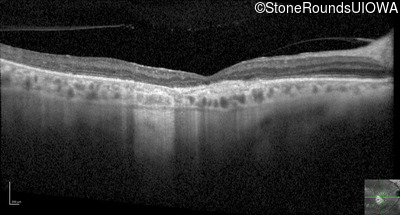

Optical Coherence Tomography - Left - 20/100

Exemplar / OCT Stack

OCT Stack

Infrared Fundus Photograph - Left - 20/100

Exemplar